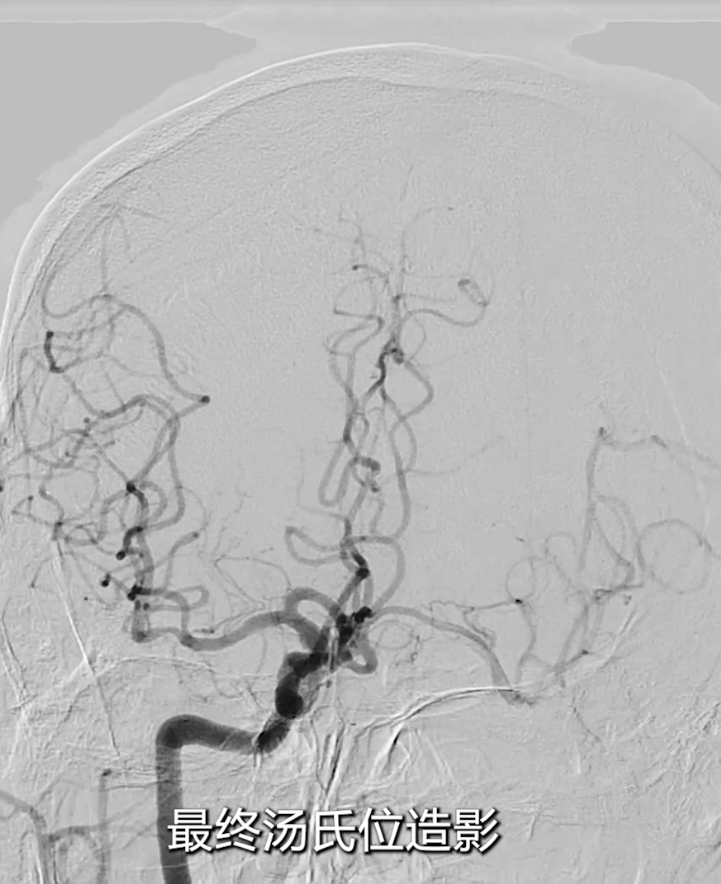

右侧颈总动脉造影(正位、汤氏位、侧位):明确右侧颈内动脉重度狭窄,病变远端直径5mm、近端直径8mm,长度约30mm,远端锚定区条件理想。

最终造影:支架血流通畅,颅内血流较术前明显改善(侧位及汤氏位对比显著);